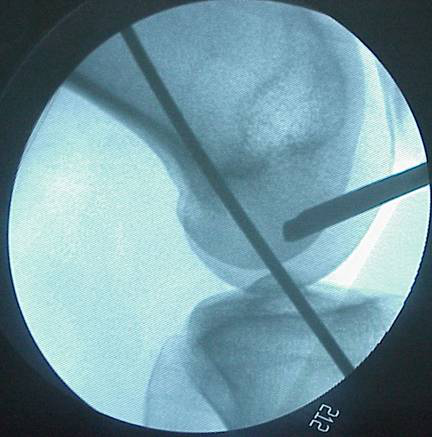

Rigidfix固定

Intrafix固定